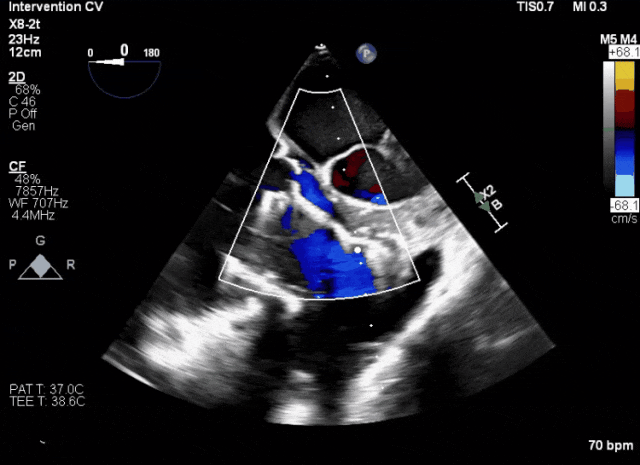

第二例患者手術難點

1、患者左心機械瓣術后,術中TEE成像有偽影干擾;2、三尖瓣重度反流,右心房、心室嚴重擴張致三尖瓣葉拴系,Gap:15.3mm,注意阻擋件抓取瓣葉操作。

術前超聲顯示三尖瓣重度反流合并拴系

術中TEE成像困難,偽影干擾